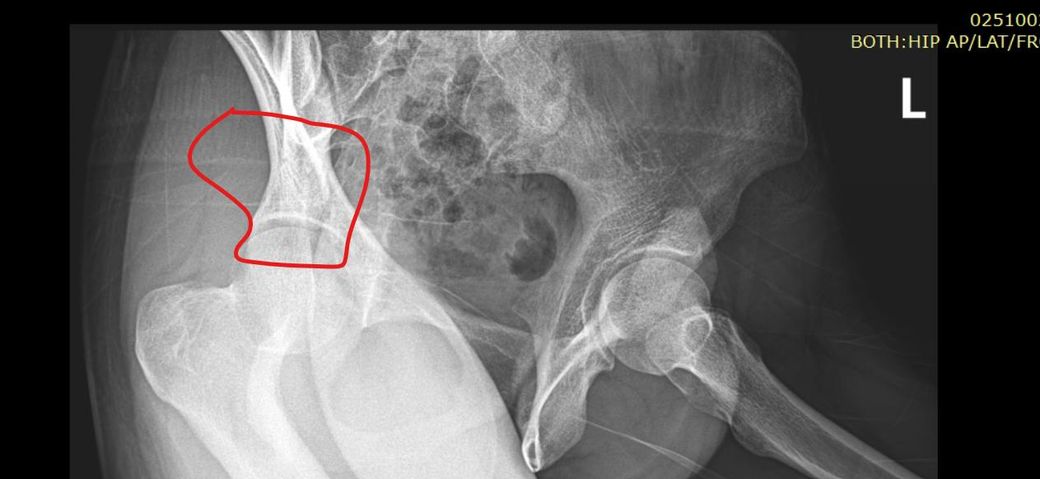

골반 골절 인거같아요 움직일떄 뚝뚝소리납니다

제가 사고나고 쫌 늧게 찍긴했습니다 근데 저기부분이 만져보면 진짜로 갈라져있어서 질문해봅니다 도와주 세요 아닌가요 ? ....

• 엑스레이 사진 한 장을 놓고 정확하게 상태 감별 및 진단을 내릴 수는 없습니다만, 올리신 사진을 통해서 보았을 때에는 딱히 따로 골절선이 보인다거나 명확한 골절 소견이 보이거나 하지 않아 보입니다. 여담으로 골반 쪽에 골절이 발생하면 보통 뚝뚝거리는 소리가 나는 정도가 아니고 보행 자체가 어렵습니다. 정황 상 보았을 때 골절이 아닐 가능성이 높아 보이는 내용입니다.

xray로 표시한 부분은 외부에서 만질수없는 부위입니다. 사진상으로도 골절선이 뚜렷이 보이진않습니다

올려주신 엑스레이에서 골절을 의심 해볼 수 있으나 저명하진 않아 불편감이 지속된다면 정형외과적 진찰과 CT 검사를 받는 것이 정확하겠습니다.